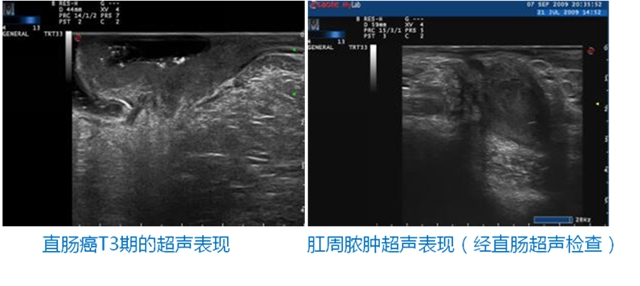

TRT33双平面腔内超声,穿透好、分辨率高,软组织层次结构显示清晰,可清楚显示肠周淋巴结、毗邻脏器和病变的关系,非常适合肛管检查及前列腺检查。

TRT33双平面腔内探头用于直肠检查优势:

1.        线阵扫查声束与肠壁和肌肉界面垂直,横断和纵切两组图像可综合分析病灶;

2.        13M探头对于组织细微结构显示分辨率高,彩色血流显示敏感度更佳;

3.        清楚地显示直肠壁各层次,对临床判定直肠癌的分期非常关键;

4.        操作简单,无创伤无辐射,动态实时显示,价格低廉。

TRT33双平面探头解决了临床其他检查存在的肠道高位肿瘤无法探及,病人较痛苦,可能产生出血、穿孔并发症,价格昂贵等不足。国内多个文献已报导,对于直肠癌的评价及判断周围组织侵犯程度确定癌肿分期,腔内超声的敏感性更高,可有效协助临床选择治疗方案。除此之外,对于肛周脓肿、肛瘘窦道定位、直肠肛门异物、对于外伤、产伤、手术伤等导致大便失禁者,双平面超声可显示括约肌损伤的程度及范围,对临床诊断、手术修补定位有明显的指导意义。